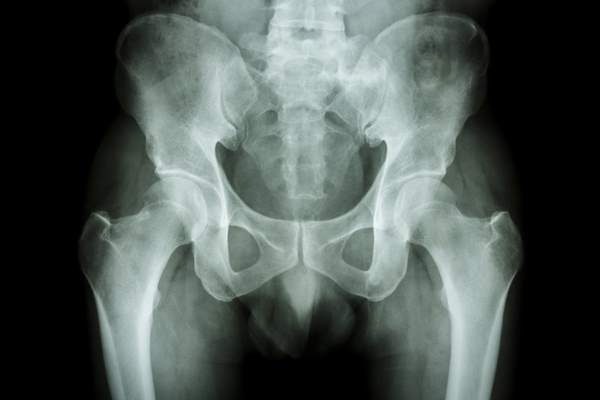

Il bacino è formato da osso sacro, ossa iliache e coccige, ed è una struttura ossea articolata, che svolge funzioni fondamentali. Esso è connesso con la colonna vertebrale, permette la locomozione, distribuisce correttamente il peso tra gli arti superiori e inferiori, sostiene la fascia addominale, contiene l’intestino, le vie urinarie, gli organi riproduttivi, importanti collegamenti vascolari, nervosi e legamenti. Proprio per questo, la rottura del bacino rischia di avere ripercussioni sull’intera struttura ossea e di lesionare anche gli organi interni.

In questi casi, si parla di frattura stabile se c’è un solo punto di rottura, di frattura instabile se i punti di rottura sono due o più: le ossa del bacino sono tutte molto grandi, motivo per cui la rottura di una o più di esse necessita di grande attenzione.

In presenza di uno o più di questi sintomi è bene effettuare con urgenza accertamenti medici. Gli esami più appropriati da svolgere per indagare la presenza e l’entità di una rottura pelvica sono la radiografia, la Tac o la risonanza magnetica, a cui possono aggiungersi ecografie, uretrografia e angiografia se ritenuto necessario dal medico.